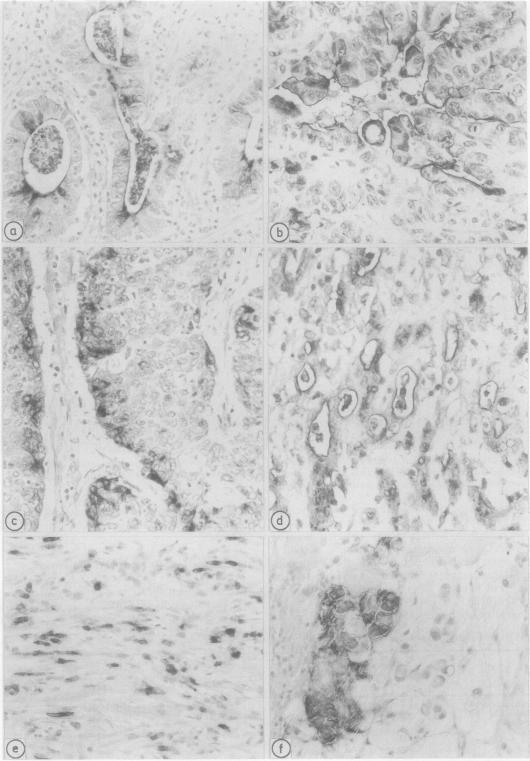

BD-5 monoclonal antibody reacted with tumour cells in 262 of 316 cases of gastric cancers, including 121 of 134 early, 141 of 182 advanced tumours (p less than 0.01), and 113 of 146 glandular, 72 of 83 diffuse, 22 of 25 mucoid, and 55 of 59 mixed tumours. No difference in reactivity was observed between metastatic and non-metastatic advanced tumours. Immunocytochemical techniques applied to light and electron microscopical specimens of colorectal mucosa and gastric cancer showed that BD-5 immunoreactive material occurred in the Golgi complex, in small clear, to dense cored, cytoplasmic vesicles, and in the glycocalix of the luminal and lateral membranes of normal and neoplastic cells in the glands, as well as in the peripheral membrane of dispersed neoplastic cells. Mucin granules stored in the cytoplasm of goblet cells were unreactive or poorly reactive. Ultrastructural features consistent with colorectal type differentiation were observed in many reactive tumours. Unreactive tumours showing ultrastructural patterns consistent with intestinal differentiation, especially of small bowel type, were also observed. Signs of intestinal differentiation, including BD-5 immunoreactivity, often occur in gastric cancer, irrespective of histological type and stage of disease.